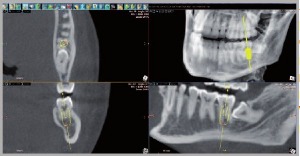

Имплантологическое планирование Имплантологическое планирование настолько интуитивно понятное и быстрое, что вы можете показать вашему пациенту предстоящую операцию сразу после получения изображения. Такая имитация впечатлит вашего пациента и сделает шанс согласия с хирургическим вмешательством максимальным. Точность имеет наибольшее значение для успешного имплантологического планирования. Система WhiteFox дает вам самый высокий уровень точности, так что безопасность пациента всегда гарантирована.

Отслеживание нервов: Определение и отслеживание нервных каналов - первый шаг в имплантологическом планировании. Определив диаметр, и окрасив в нужный цвет, нервы будут видны во всех сечениях и визуали